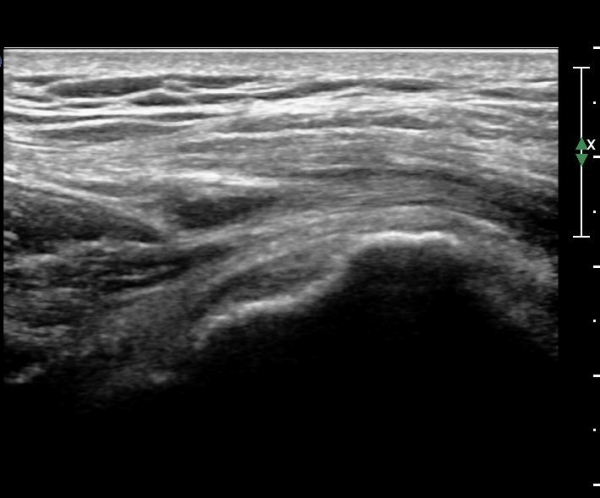

ŽÃËÀÚ¸¦ ¾ÕÂÊÀ¸·Î À̵¿ÇÏ¿© ´ëÀüÀÚ ¾ÕÂÊ È¾´Ü¸é°Ë»ç¿¡¼­ ¼ÒµÐ±ÙÈûÁÙ°ú Àå°æÀÎ´ë »çÀÌ¿¡

¼Ò·®ÀÇ ¼ö¾×Àú·ù°¡ °üÂûµÇ°í(»çÁø 4)

ŽÃËÀÚ¸¦ ¸Ó¸®ÂÊÀ¸·Î À̵¿ÇÏ´Ï ¼ö¾×Àú·ù°¡ ´õ ¸¹ÀÌ °üÂûµÈ´Ù(»çÁø 5).